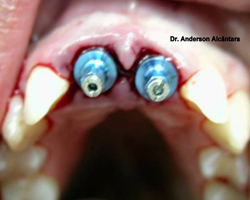

Removemos as raízes perdidas e constatamos a fratura. Instalamos 2 implantes, moldamos e enviamos ao protético para confecão da prótese.

No dia seguinte o paciente volta, removemos o cicatrizador e instalamos a prótese sobre implante provisória. Ela ficará 06 meses em função. Após esse período removemos a provisória e instalamos a definitiva que é confeccionada de porcelana. Neste caso após concluírmos o trabalho o paciente passa fio dental e escova normalmente entre os dentes.